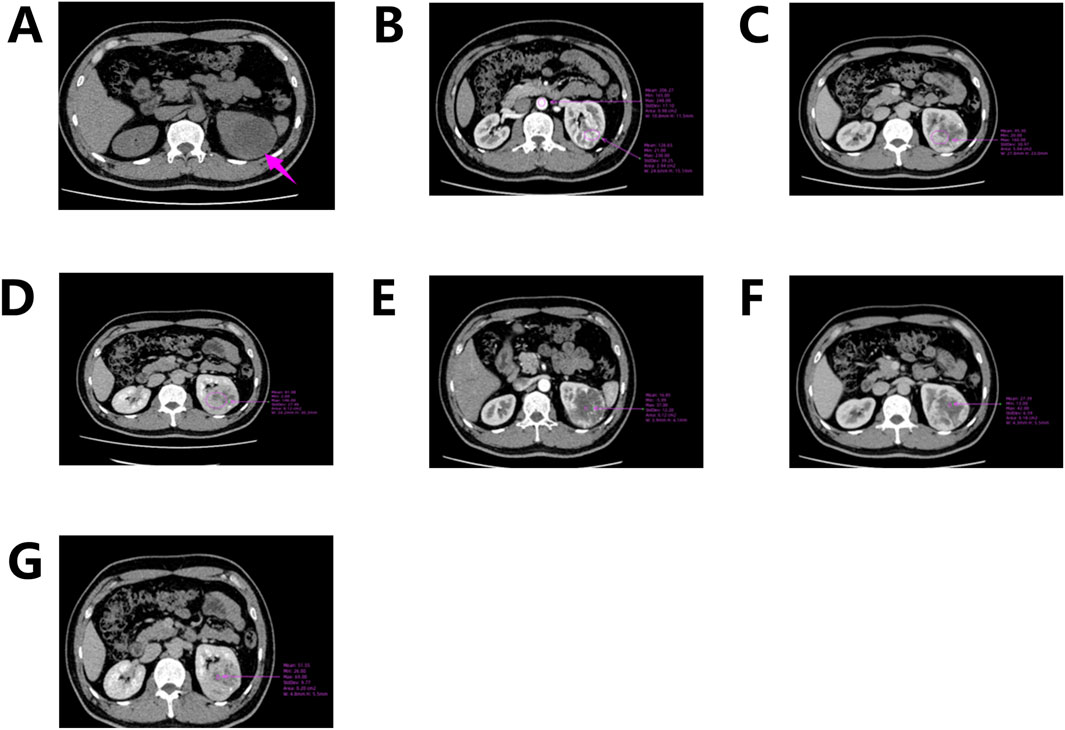

Abdominal computed tomography (CT) with contrast enhancement and three-dimensional reconstruction revealed a slightly hypodense lesion with localized calcification in the upper pole of the left renal parenchyma. The lesion measured approximately 6.9 cm × 5.7 cm × 5.6 cm (Figure 1A) and extended beyond the renal contour. The mass was well-circumscribed, roundish, and encapsulated, with no evidence of peripheral invasion. Scattered calcifications were noted. Contrast-enhanced imaging demonstrated predominantly marginal enhancement with a “centripetal filling” pattern, persistent enhancement during the medullary phase, and heterogeneous enhancement during the cortical phase, with the lesion appearing less dense than the adjacent renal parenchyma (Figures 1B–G). “Centripetal filling” is defined as a dynamic contrast enhancement pattern in which contrast agent gradually spreads from the periphery of the tumor toward the center in multiple CT scans.

Figure 1. CT scan of the left kidney. (A) CT scan shows a mass in the upper pole of the left kidney; (B) Corticomedullary Phase; (C) Nephrographic Phase; (D) Excretory Phase; (E–G) Enhanced CT shows a dynamic “centripetal filling” pattern.

In this case, CT revealed a heterogeneously enhanced, roundish solid mass with scattered calcifications, predominantly located along its periphery. While Nonaka et al. previously described calcifications localized within cystic spaces, the calcifications in our case were primarily concentrated at the tumor margins (Nonaka et al., 2007). Contrast-enhanced imaging demonstrated marked enhancement of the peripheral solid component (maximum CT value ∼230 HU; abdominal aorta CT value ∼248 HU), with cortical phase enhancement approaching aortic CT values (Figure 1B). During the medullary phase (CT value ∼160 HU) and excretory phase (CT value ∼146 HU), enhancement diminished slightly (Figures 1C–D). The central hypodense area on non-contrast scans exhibited mild delayed enhancement during cortical, medullary, and excretory phases (CT values ∼37, 42, and 69 HU, respectively), demonstrating progressive “centripetal filling” (Figures 1E–G).